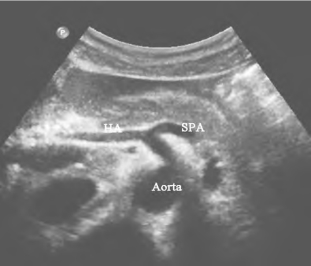

1.36.4四、腹腔大血管